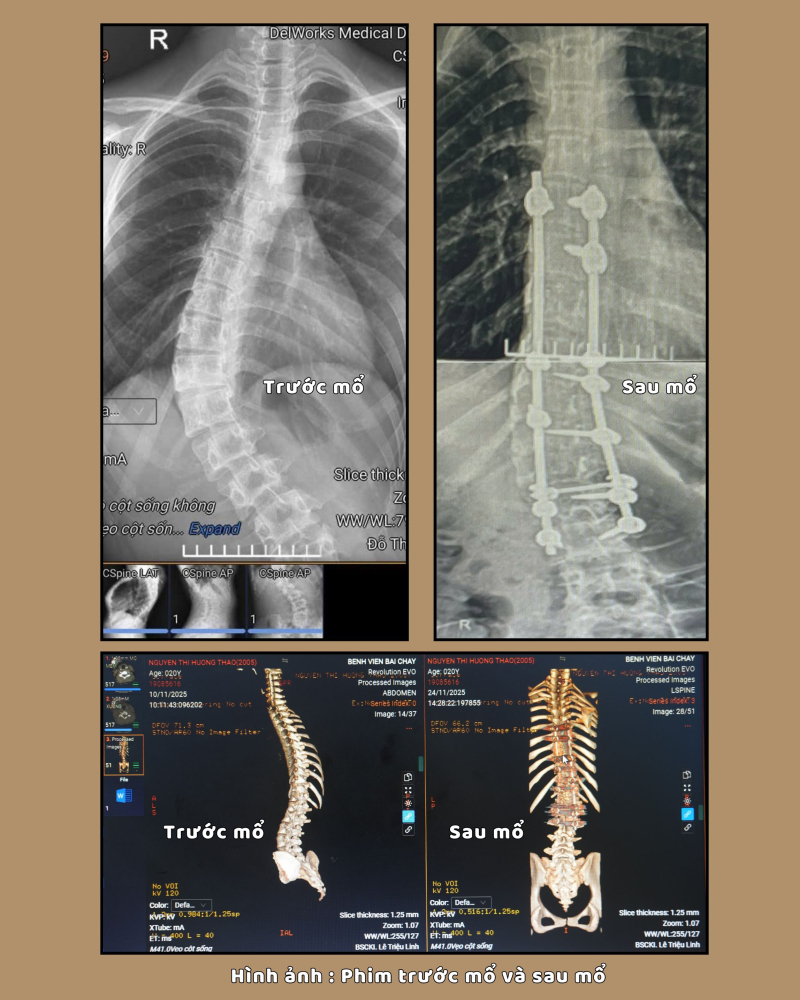

Khi vào viện được các bác

sĩ thăm khám và cho làm các xét nghiệm cần thiết. Kết quả chụp cắt lớp vi tính

cho thấy: Hình ảnh vẹo cột sống/nẹp cố định đốt sống từ D6 đến L3. Gãy cung sau

một số thân đốt sống và được chẩn đoán: Vẹo cột sống mức độ nặng, có chỉ định

phẫu thuật chỉnh vẹo cột sống.

Kíp phẫu thuật do bác sĩ CKII Lê Triệu Linh, Phó trưởng khoa Ngoại thần kinh – Lồng ngực, Bệnh viện Bãi Cháy cùng ê kíp phẫu thuật đã tiến hành phẫu thuật giải phóng cấu trúc biến dạng, chỉnh trục cột sống và cố định bằng các thanh nẹp – vít chuyên dụng. Sau mổ, cột sống được đưa về trục cân đối tự nhiên, giải phóng áp lực lên các rễ thần kinh.

Hiện tại sau 1 tuần phẫu thuật, bệnh nhân phục hồi tốt, đi lại nhẹ nhàng, cột sống thẳng hơn, các cơn đau giảm rõ rệt và đặc biệt là tâm lý tự tin hơn trong sinh hoạt cũng như giao tiếp hàng ngày.